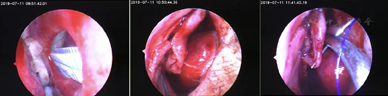

麻醉及手术方法:患者取平卧位,常规消毒铺巾,双侧鼻腔内黏膜以1%丁卡因棉片表面麻醉4次,2%利多卡因3ml加0.1%肾上腺素0.1ml行左侧鼻腔黏膜及皮肤交接处局部浸润麻醉,待麻醉效果满意后用小圆刀行皮肤黏膜切口,切口向上延伸至鼻顶,向下向鼻底部延伸,用带吸引的剥离子向鼻底部剥离黏骨膜。骨折内移下鼻甲,扩宽下鼻道,将下鼻道及部分鼻腔外侧壁的黏骨膜一并分离。沿着下鼻甲根部切开黏骨膜,避开泪道在下鼻道开口,先后达后鼻孔缘,表麻下冲洗泪道见下鼻道泪道开口通畅。用锐性剥离子行鼻中隔穿孔周边黏膜仔细剥离,测量剥离后的新鲜穿孔创面最大直径约1.5cm,向上牵拉带蒂的鼻底鼻腔外侧壁黏膜瓣,完整无张力覆盖穿孔周边可。用4-0可吸收线固定黏骨膜瓣覆盖全部穿孔,前方蒂固定在前鼻孔切口周边,对位缝合切口缘(图2)。检查术腔未见异物残留,各黏膜色泽正常,用倍复舒及明胶海绵填塞下鼻道的骨质暴露,明胶海绵保护固定黏膜瓣,术毕,术后患者回病房休息。